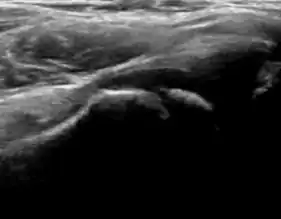

During childhood, ultrasound is a quick method to assess hip pain and quite often may be used to avoid use of irradiating techniques, such as radiography or CT. Ultrasound allows evaluation of joint effusion, synovial thickening and neovascularity, the bone/cartilage contour, and the femoral head-neck alignment. Although sonography is extremely sensitive in detecting increased synovial fluid, it is nonspecific and cannot be used with accuracy to determine the type of fluid. Transient synovitis of the hip, despite being the most frequent cause of pain in children between 3 and 10 years, remains a diagnosis of exclusion. It usually shows anechoic fluid, but echogenic fluid can also be found. The effusion is considered pathologic when it is measured at >2 mm in thickness. The differential diagnosis is wide, including osteomyelitis, septic arthritis, primary or metastatic lesions, LCPD, and SCFE. Discrimination from septic arthritis is challenging, often requiring joint aspiration. In septic arthritis, US is able to demonstrate a hip joint effusion, synovial thickening, and cartilage damage, although the appearances are nonspecific.[1]

A step between the head and the physis can be detected in children with SCFE, while abnormalities in the femoral head contour may suggest the presence of LCPD. In both cases, radiographs are mandatory to confirm diagnosis and severity (Figure 12).[1]

Figure 12:

-

Normal ultrasound appearance of the femoral head-neck junction. -

Joint effusion in transient synovitis of the hip. -

Flattening of the femoral head in a patient with Perthes disease. -

Step in the femoral head-neck junction in a patient with SCFE.